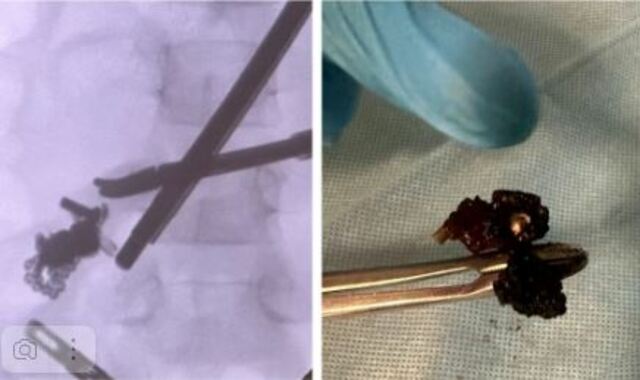

Чӑваш Енри тухтӑрсем магнит ҫӑтса янӑ ачасене пулӑшнӑ.

Республикӑн ача-пӑча клиника больницинче пӗлтернӗ тӑрӑх, сывлӑх сиплев учрежденийӗн йышӑнупа диагностика уйрӑмне магнит ҫӑтса янӑ ачасем час-часах лекеҫҫӗ. Кашни ҫул — 15 ача таран.

Тухтӑрсем пӗлтернӗ тӑрӑх, ашшӗ-амӑшӗ тӗпренчӗкӗсене магнит шариксенчен тӑракан пуҫватмӑшсем туянса пама юратать. Пӗчӗкскерсем конструктор пайӗсене ҫӑтса яраҫҫӗ. Харӑсах темиҫе магнит хыпса лартсан вӑл хырӑмран хӑй тӗллӗн тухаймасть, операци тума тивет.

Юлашки икӗ эрнере ҫеҫ ҫавӑн пек хӑтланнӑ икӗ ачана тухтӑрсем патне илсе пынӑ. Магнитсем пӗрлешсе ярса хырӑмра перитонит пуҫланса кайнӑ. Вӗсен пурнӑҫне тухтӑрсем ҫӑлса хӑварнӑ.